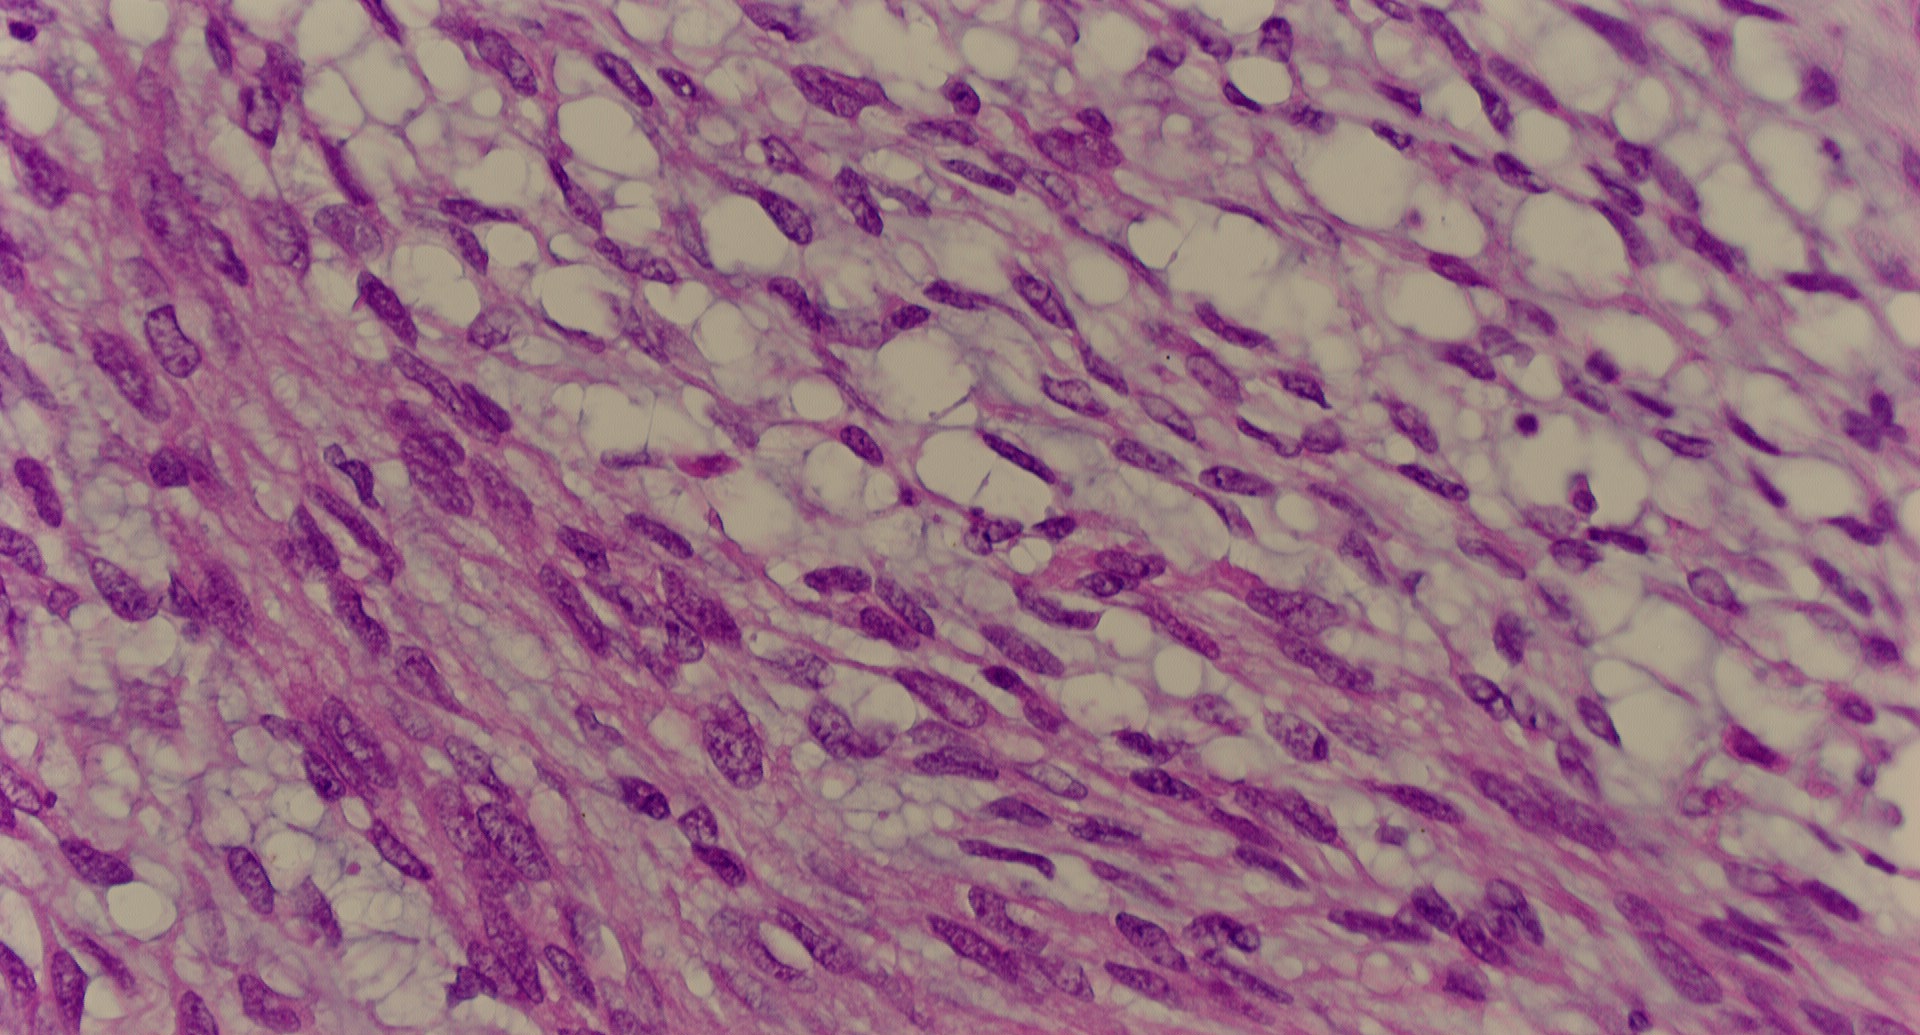

標本14

標本14の説明